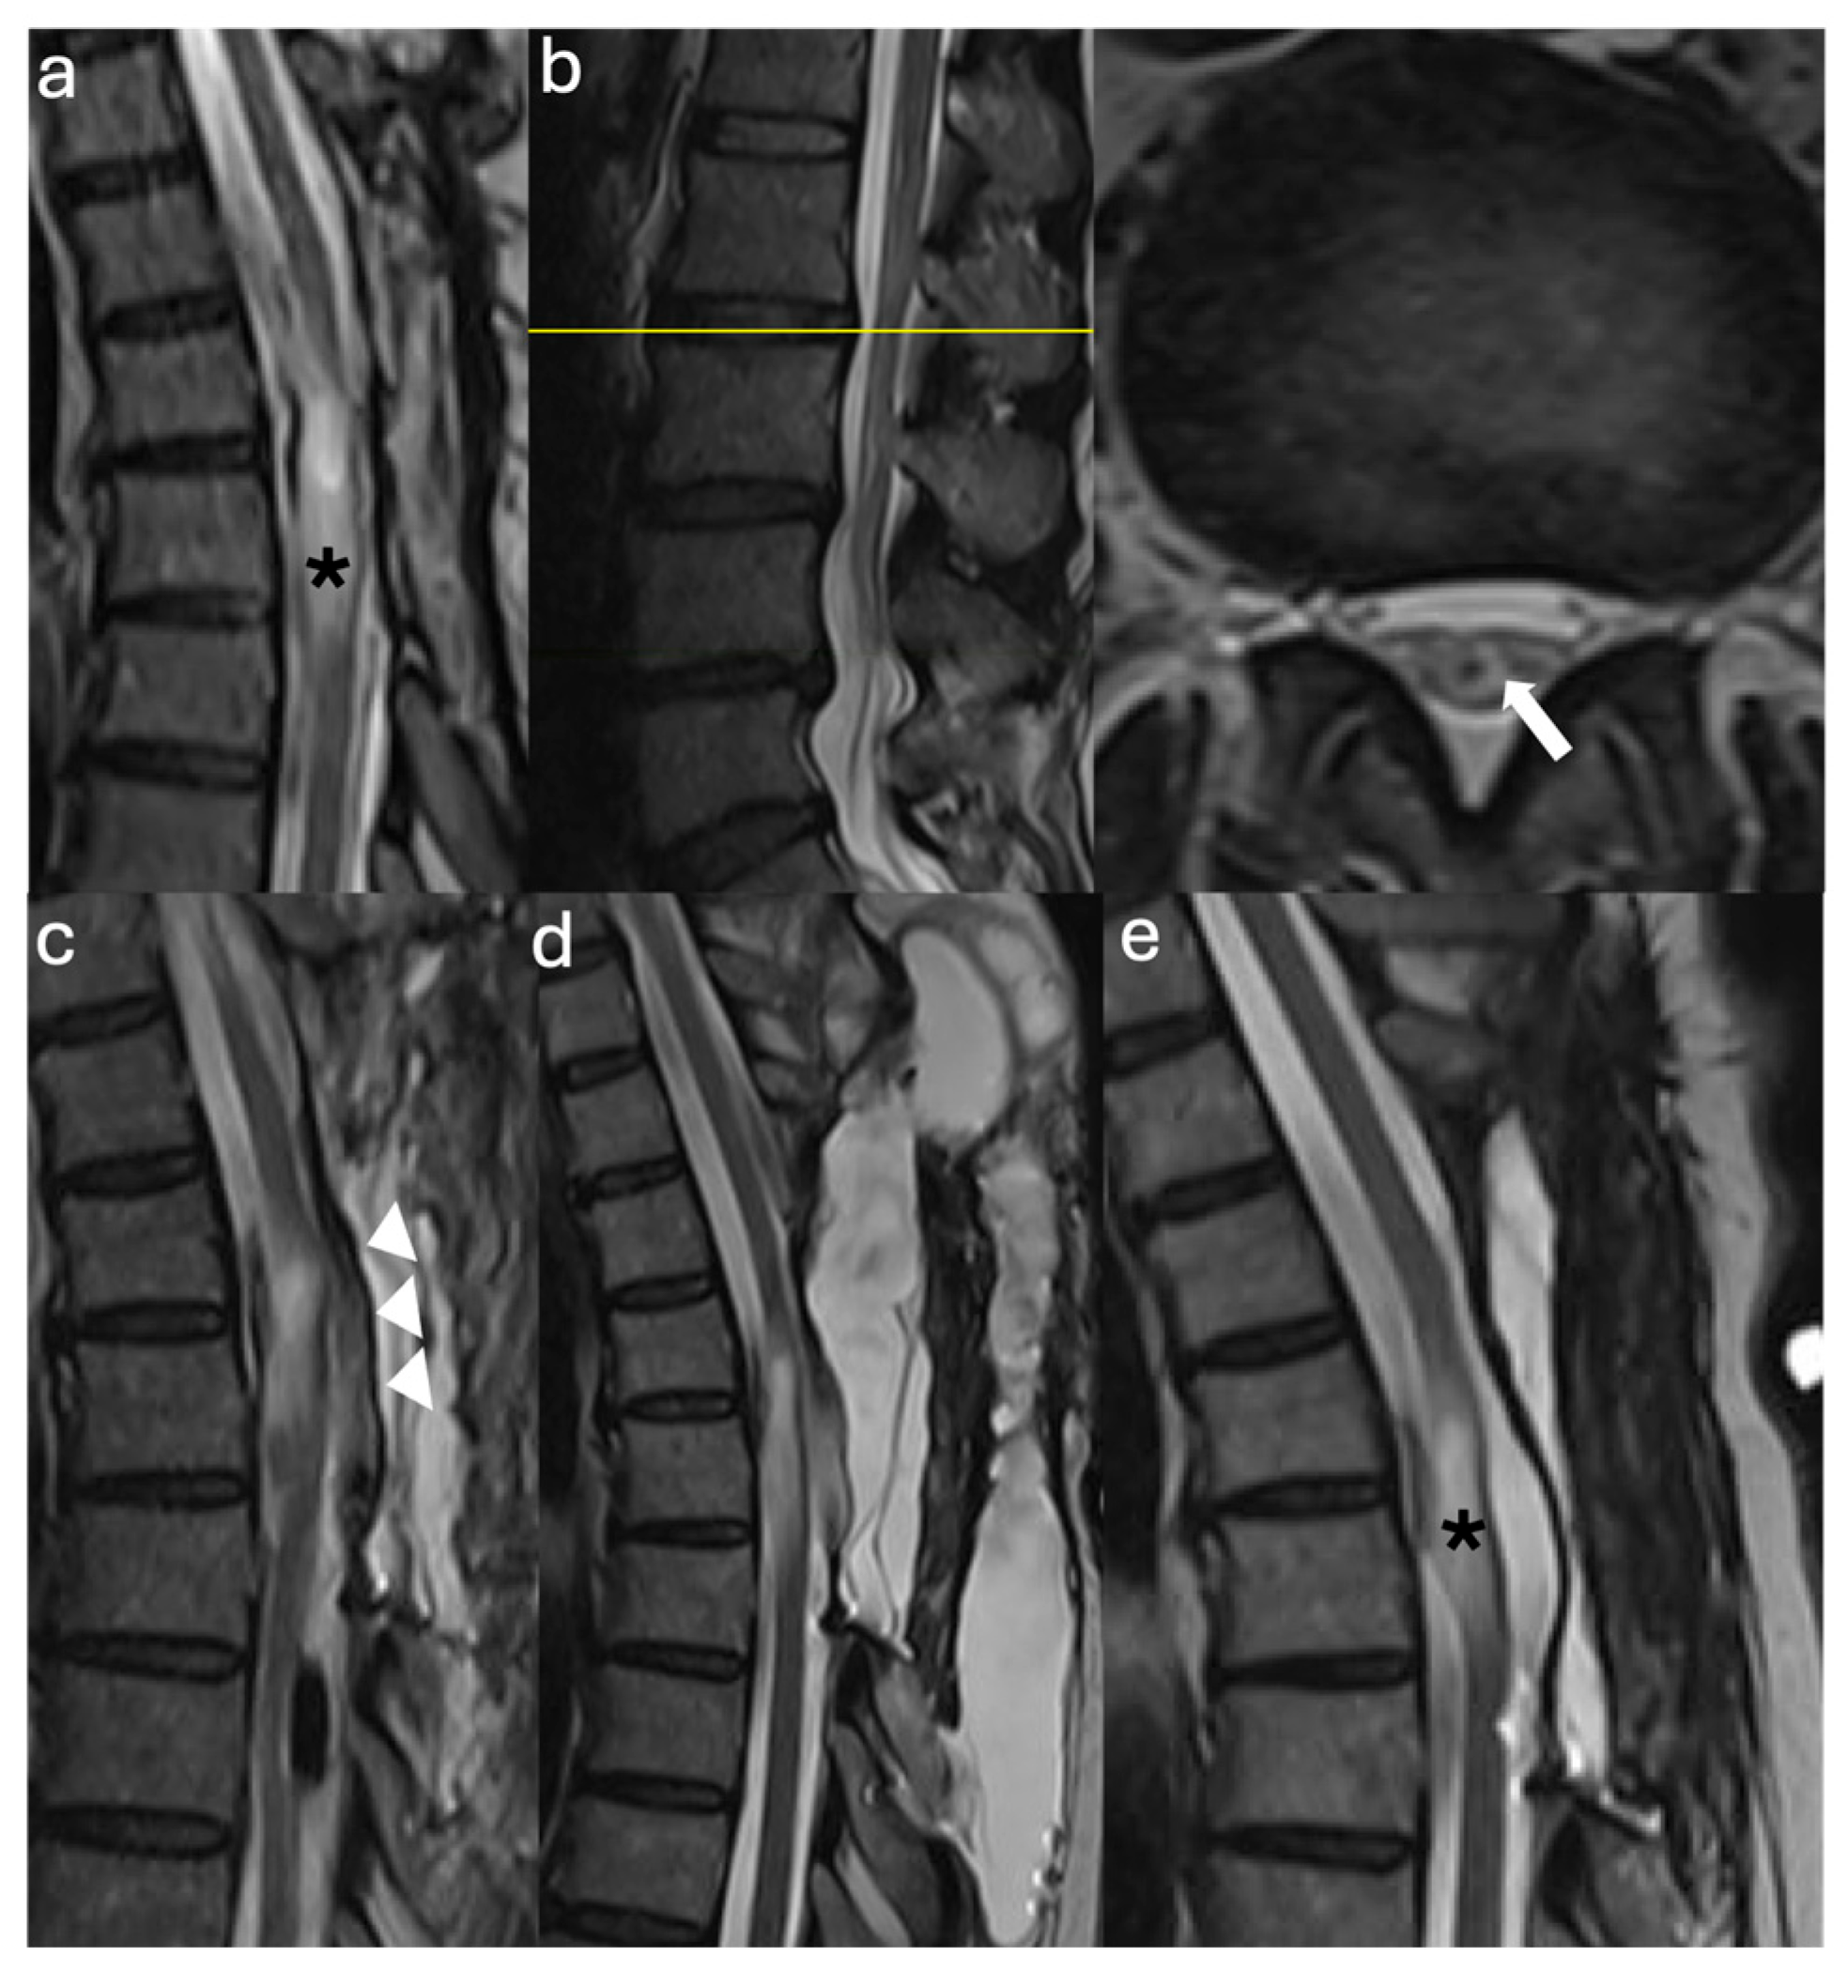

3.2.1. Case #1

3.2.2. Case #2

3.2.3. Case #3

3.2.4. Case #4

3.2.5. Case #5